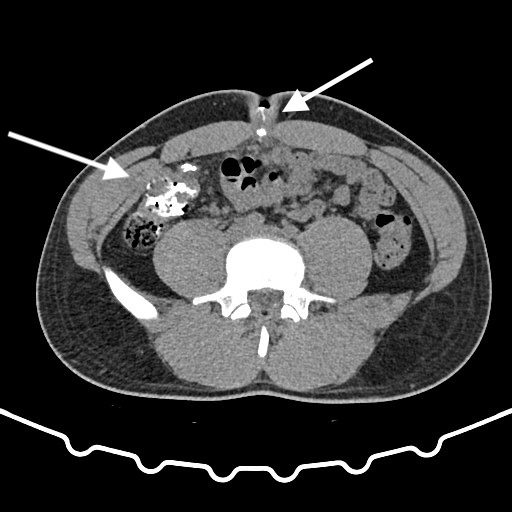

Three years after the appendectomy, the patient returned to the emergency department due to periumbilical pain and erythema that had persisted for three months. On further questioning the patient also reported intermittent diarrhea for one week, with no accompanying vomit or fever. During the physical examination, erythema and pain upon palpation of the umbilicus were observed. The blood tests showed no significant changes. Imaging with a CT scan and fistulogram through the umbilical granuloma allowed for the identification of a fistulous tract to a pericecal collection (figure 1-3). The patient was admitted and started on empiric antibiotic therapy with piperacillin and tazobactam.

Fig. 1-2: CT scan with fistulogram through the umbilical granuloma showing the fistulous tract to the cecum (white arrow) - axial view.